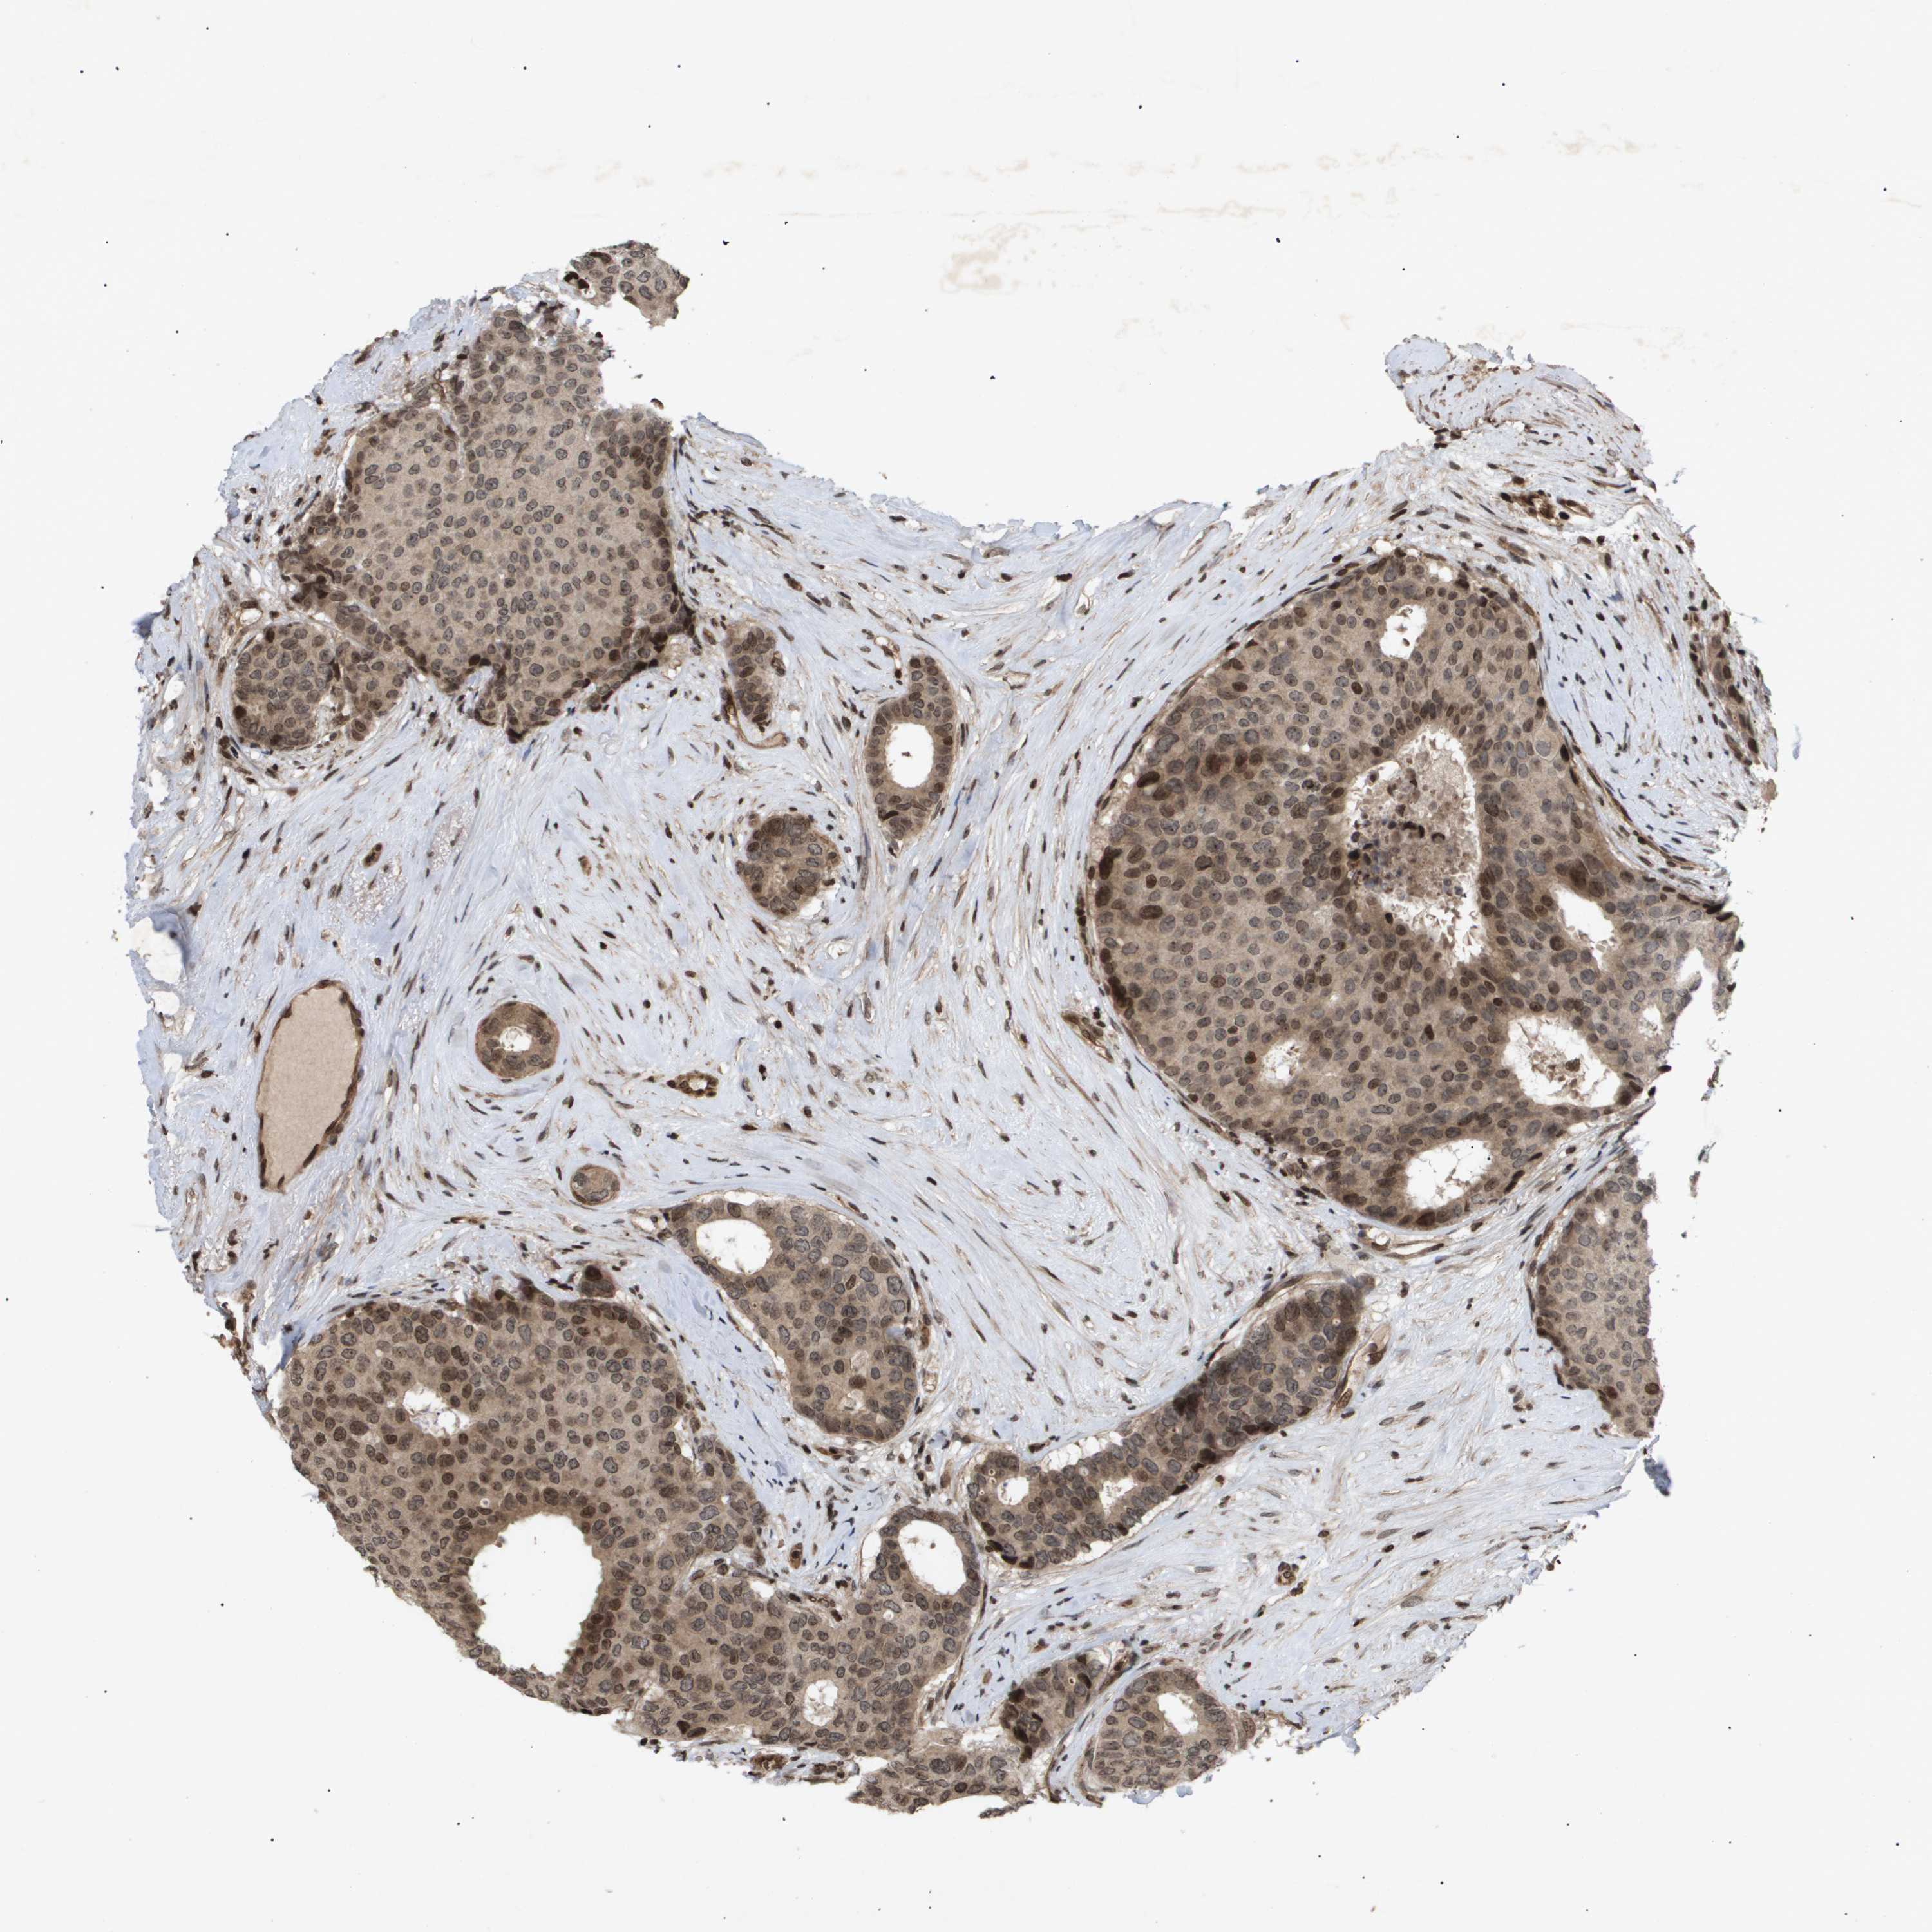

CANCER BREAST CANCER Show tissue menu

BRCA TCGA BRCA VALIDATION PROTEIN EXPRESSION

ANTIBODIES

AND

VALIDATION